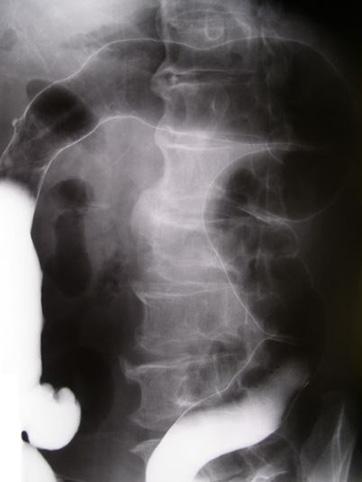

A case of ileocecal cancer associated with old tuberculosis.

[ Image ID:10168 ]

Criteria of Hist.Classification

Malignant epithelial tumor/Mucinous carcinoma

Technique, Method

X-ray